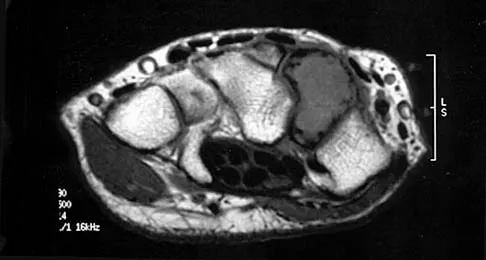

Embolic material generated during total knee arthroplasty (TKA) shown in Figure 29 is composed of which of the following substances?

Explanation